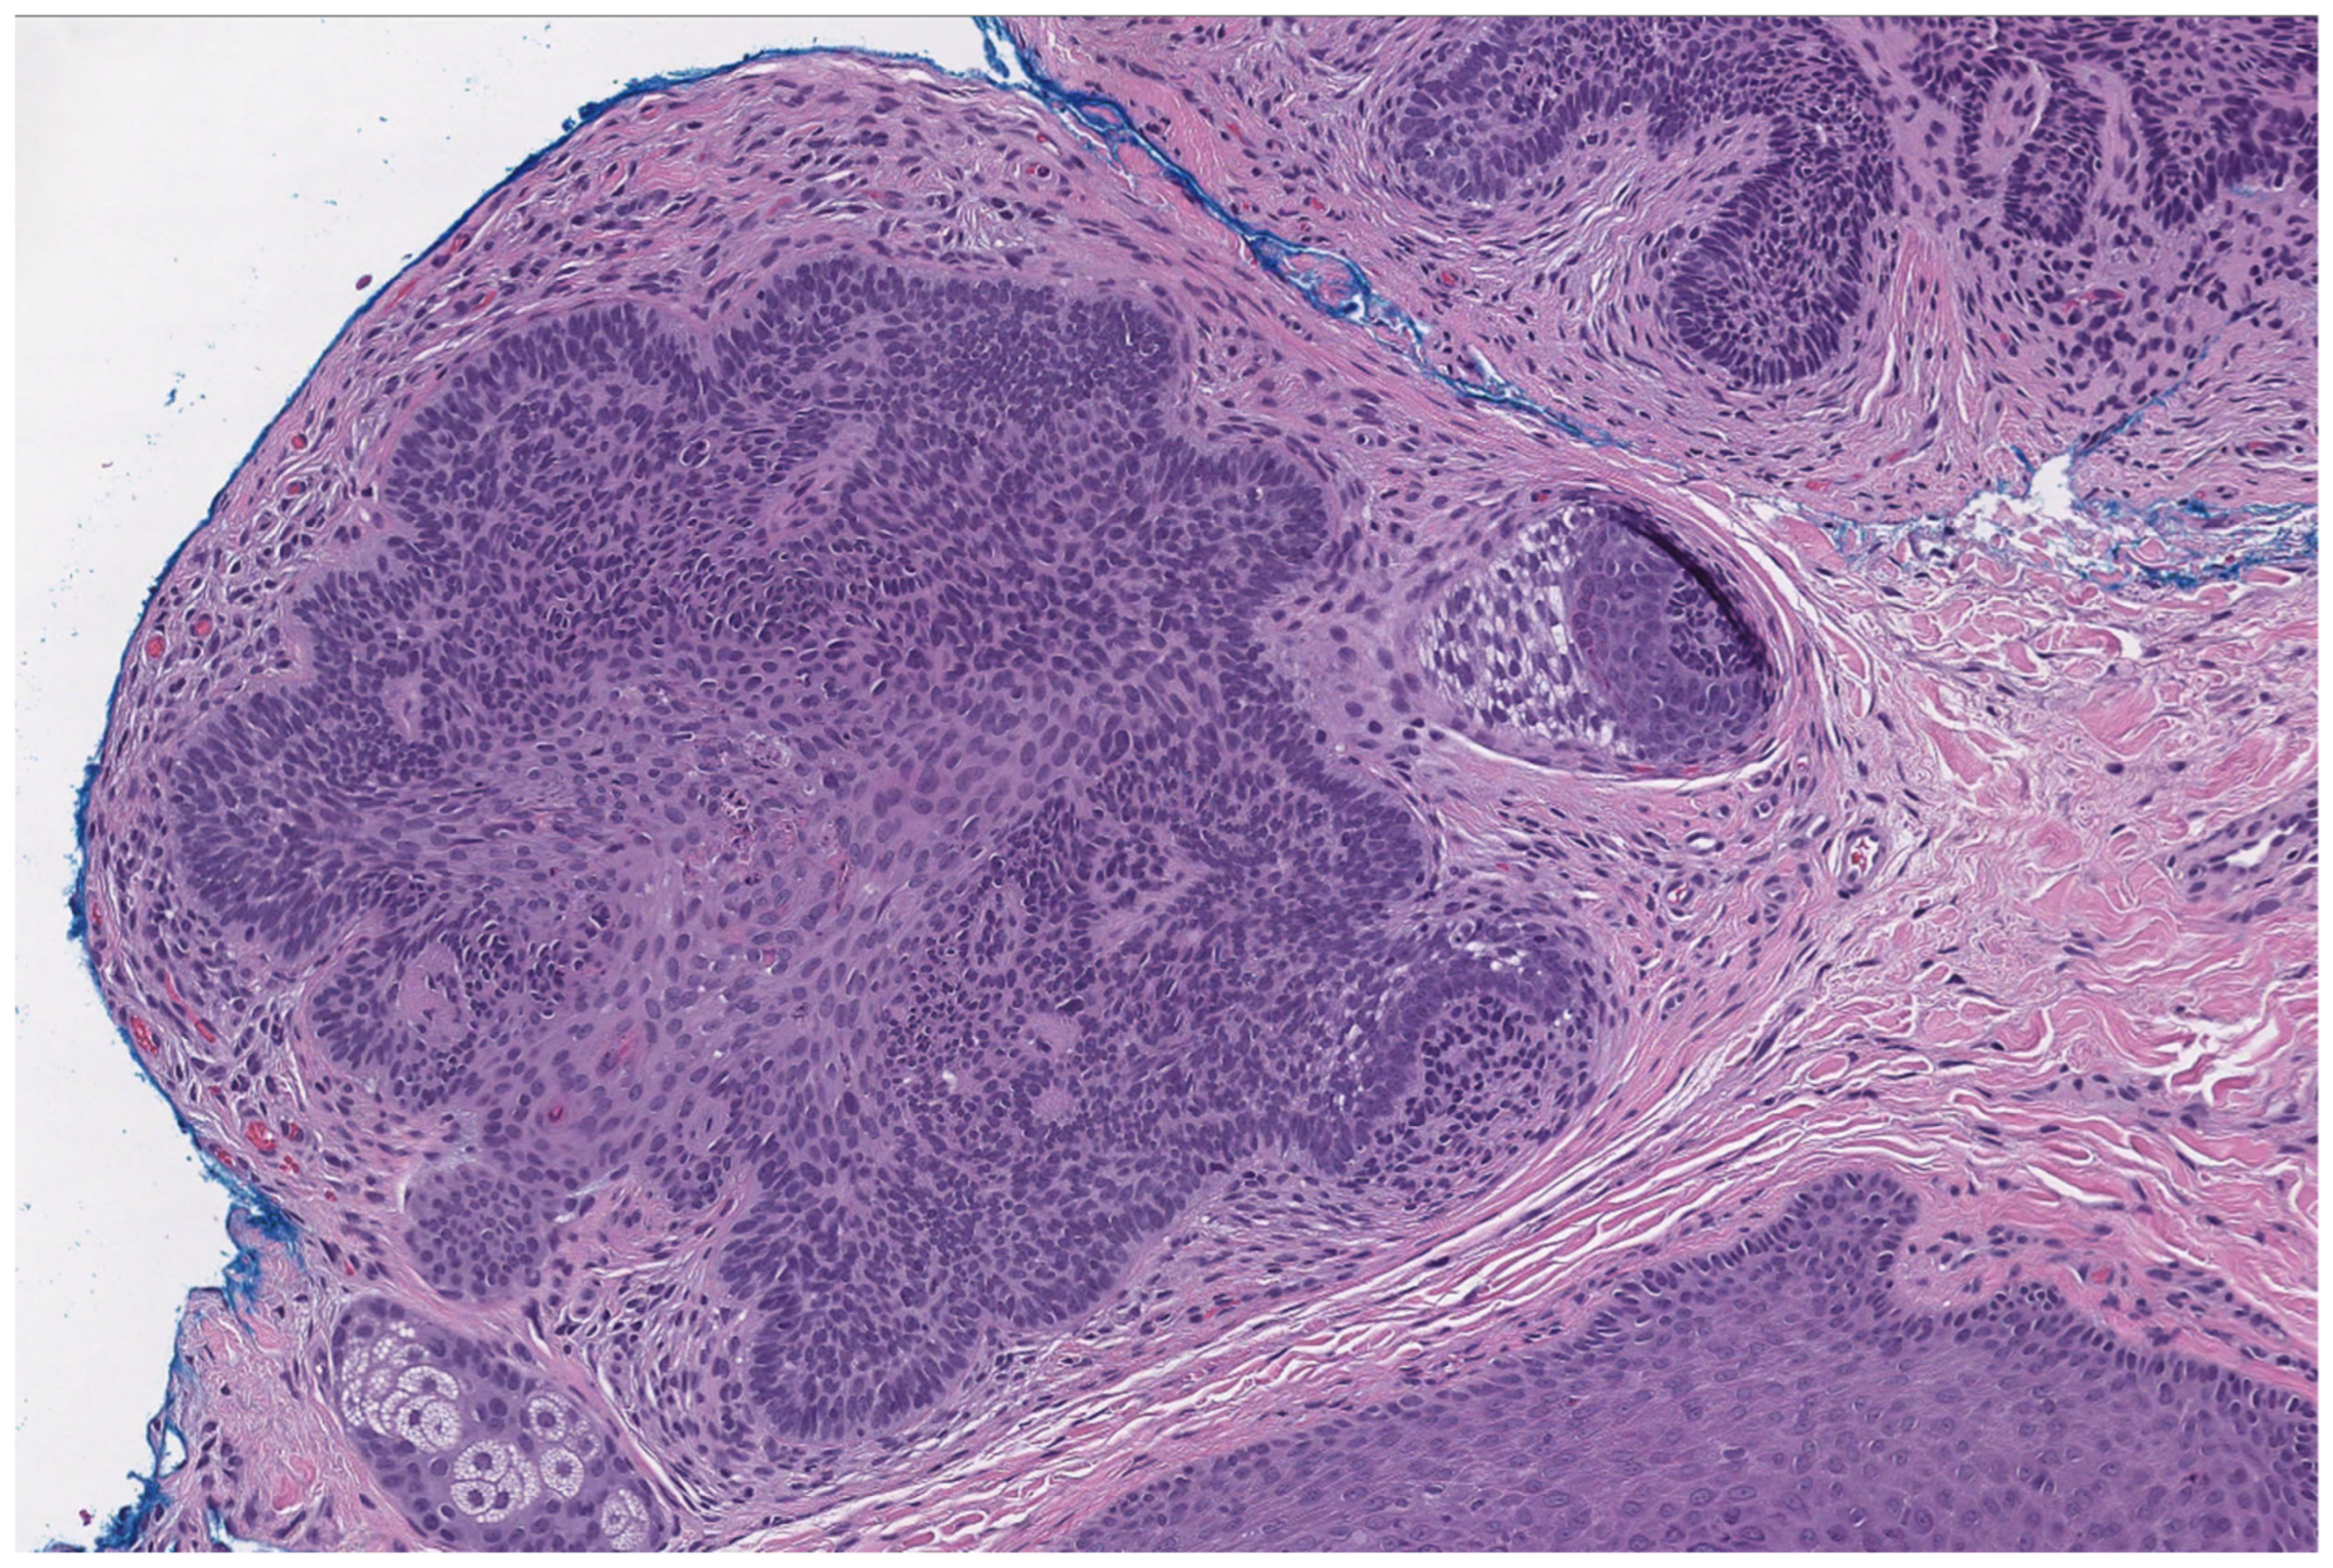

2.4. Trichoepithelioma